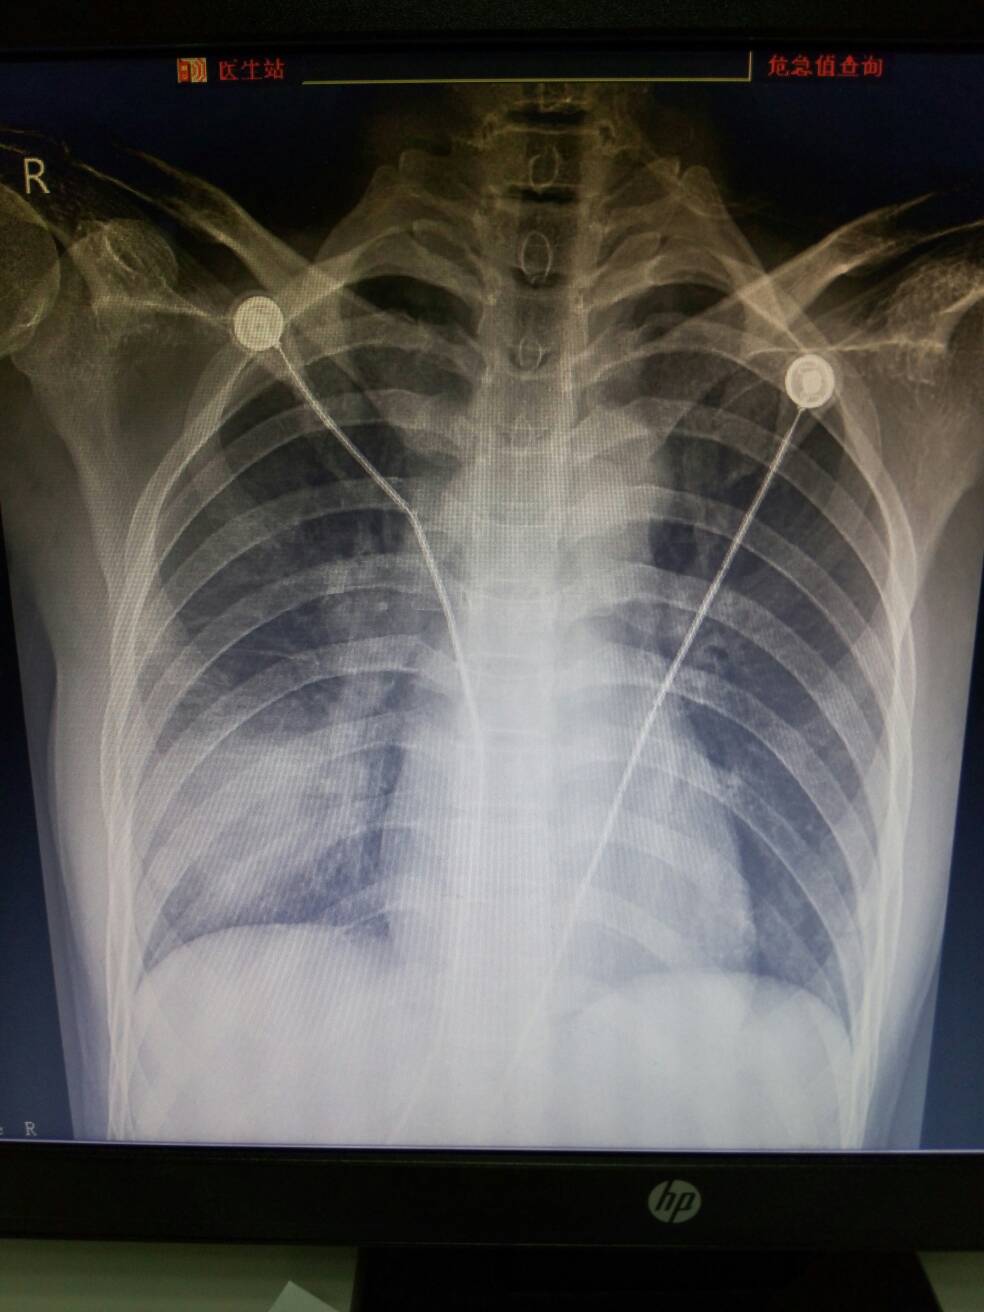

右下肺见大片状密度增高影,边缘模糊。右肺门角消失,密度增浓、增大。考虑右下肺及右肺门区炎症。

右下肺及右肺门区炎症